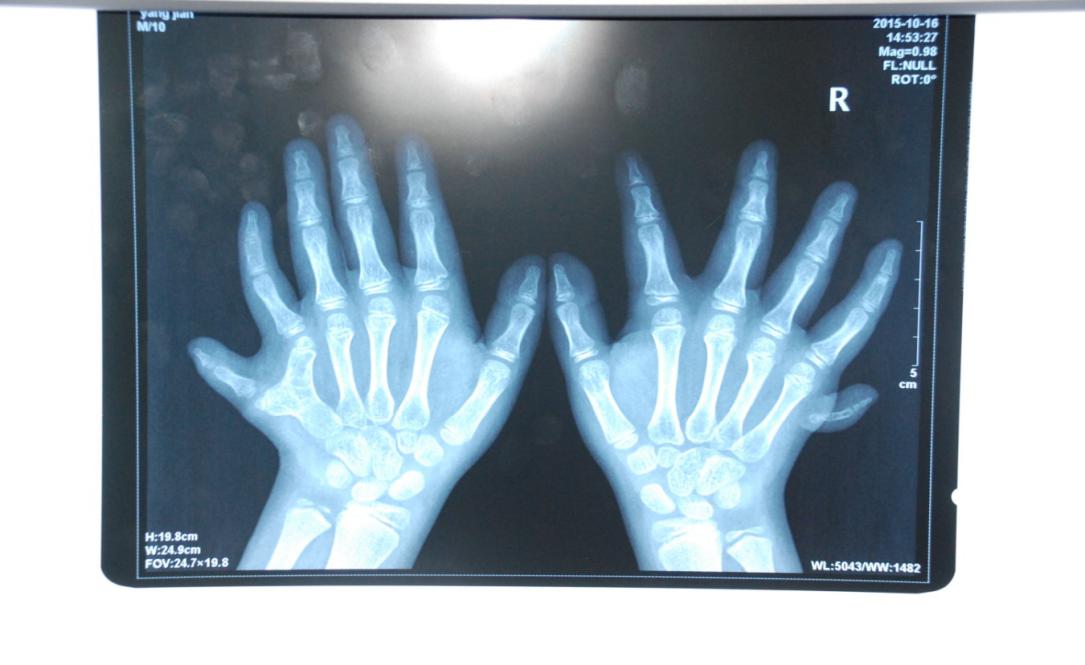

廈門眼科中心小兒眼科修陽暉博士在日常的診療過程中就接診了不少這樣的的特殊家庭,讓其尤為印象深刻的就是一年前接診的BBS綜合征患者。當(dāng)時(shí)來院就診的是一對(duì)親兄弟,之前已在多家醫(yī)院做過檢查,因其均有較大散光和斜視,肉眼下眼底檢查未見異常,故外院均診斷為弱視,這也符合眼科門診常規(guī)的診斷邏輯與思維。但由于兄弟倆均有智力發(fā)育遲緩、特殊面容及四肢均有六指和六趾的特異體征引起了修陽暉博士的警覺:會(huì)不會(huì)是一種特殊遺傳性疾病或綜合征?后續(xù)的檢查結(jié)果進(jìn)一步證實(shí)了修陽暉博士的懷疑---患兒均有夜盲,ERG、VEP及OCT檢查顯示雙眼的視網(wǎng)膜神經(jīng)上皮層結(jié)構(gòu)及功能均明顯異常。由于之前未遇到此種病例,修陽暉博士在診斷一欄寫下視網(wǎng)膜色素變性并打上了個(gè)問號(hào),同時(shí)留下了病人的聯(lián)系方式。

BBS綜合征(Bardet-Biedl綜合征)是一種主要累及纖毛結(jié)構(gòu)與功能的罕見常染色體隱性遺傳性疾病。纖毛分布于哺乳動(dòng)物體內(nèi)的大多數(shù)細(xì)胞,它是一種廣泛存在于各種細(xì)胞表面的細(xì)胞器,體型微小但結(jié)構(gòu)復(fù)雜、作用強(qiáng)大,能感知細(xì)胞外機(jī)械和化學(xué)信號(hào)變化并協(xié)助其轉(zhuǎn)導(dǎo)到細(xì)胞內(nèi)部從而引起細(xì)胞應(yīng)答。高等動(dòng)物的視覺、觸覺、嗅覺、聽覺的傳遞都依賴于體內(nèi)外正常的纖毛結(jié)構(gòu)和功能。因此BBS綜合征常累及全身多個(gè)系統(tǒng)和器官,在臨床上主要表現(xiàn)為:視網(wǎng)膜色素變性、智力發(fā)育異常、向心性肥胖、多指(趾)、性腺發(fā)育異常、腎臟異常。除此之外還有許多諸如:語言發(fā)育障礙、聽力異常、嗅覺異常、斜視、白內(nèi)障、散光、牙齒發(fā)育異常、短指(趾)、并指(趾)、肝纖維化、糖尿病、高血壓等表現(xiàn)。